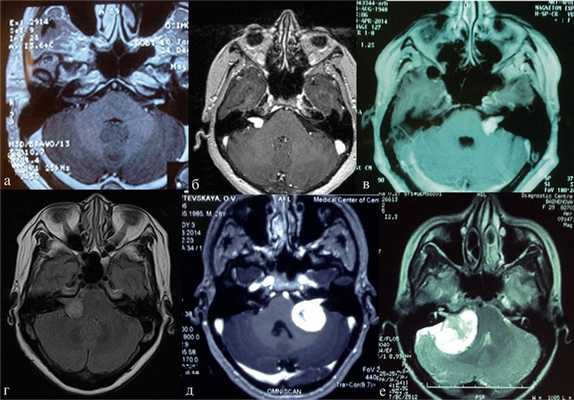

Наиболее информативным методом выявления вестибулярных шванном является МРТ головного мозга с контрастным усилением в режиме Т1 и Т2. Это исследование позволяет определить размеры опухоли, наличие перитуморозного отека, наличие признаков окклюзионной гидроцефалии, которая может быть следствием сдавления опухолью IV желудочка. Кроме этого МРТ позволяет провести дифференциальную диагностику с другими опухолями схожей локализации (чаще с менингиомой задней грани пирамиды височной кости). Еще одним стандартом диагностики является КТ в костном режиме. Независимо от снижения слуха стандартом является проведение аппаратной аудиографии.

В работе проведен анализ результатов обследования и хирургического лечения 90 пациентов с верифицированными вестибулярными шванномами преимущественно больших размеров, оперированных в РНХИ им. проф. А.Л. Поленова с 2013 г. по 2014 г. Нами заложено два основных направления в нашей работе - это хирургическое и нейрофизиологическое. Первое направление включало изучение топографо-анатомического варианта опухоли, распространенность новообразования и степень ее биологической агрессивности. Любое хирургическое вмешательство тщательно планировалось с использованием современных методов нейровизуализации, позволяющих оценить взаимоотношение опухоли с магистральными сосудами и краниальными нервами. Задачами хирургии является сочетание максимальной радикальности с сохранением функции черепных нервов. При больших и гигантских шванномах использовался стандартный ретросигмовидный доступ, но с укладкой больного в сидячем положении, что обеспечивает на наш взгляд, лучший обзор опухоли, баланс ликвородинамики, меньшую тракцию полушария мозжечка и адекватную декомпрессию ствола головного мозга, непрерывное «промывание» раны как дополнительный метод гемостаза, исключающий скопление крови в ране и окклюзию цистерн. Второе направление сводилось к многофункциональному интраоперационному мониторингу. Все пациенты были разделены нами на две группы: 1-я группа - глухие, 2-я группа- с сохранным слухом. Возраст пациентов варьировал от 24 до 83 лет, средний возраст составил 45,4 ± 3,2 г. Отмечено преобладание женщин - 71 (78,8 %), мужчин - 19 (21,1 %). Преимущественное расположение опухоли было правосторонним - 62 (68,8 %), левосторонним - 28 (31,1 %). Длительность заболевания колебалась от 1 года до 17 лет. Размеры опухоли определялись по данным КТ и/или МРТ. Размеры опухоли варьировались от 25 мм до 42,1 мм. В первую группу (глухие) вошли - 70 (77,8 %) пациентов, во вторую группу (с сохранным слухом) - 20 (22,2 %) пациентов. В нашей работе мы использовали общепринятые классификации вестибулярных шванном (Koos, M. Sammi). У большинства пациентов, поступающих в стационар, выявлены вестибулярные шванномы больших и гигантских размеров (Koos IV). Причины этого явления весьма разнообразны и требуют отдельного целенаправленного исследования. Радикальность удаления опухоли оценивалась по Токийской классификации (1998 г.). Всем пациентам проводился дооперационный диагностический стандартный клинический комплекс, включающий в себя: неврологическое, отоневрологическое, нейроофтальмологическое, нейрофизиологическое обследование. У пациентов с сохранным слухом проводили в дооперационном периоде аудиометрию, подтверждающую и определяющую степень сохранности слуха по шкале Gardner-Robertson [4, 5, 6]. Функцию лицевого нерва при поступлении и в раннем послеоперационном периоде оценивали по шкале House-Brackmann [5, 6, 7]. Тяжесть состояния в момент поступления в отделение и при выписке оценивали по шкале Karnofsky. У 2 (2,2 %) больных состояние оценивалось в 50 %, в 60-70 % у 45 пациентов (женщин - 42 (46,6 %); мужчин - 3 (3,3 %)), в 80-90 % (мужчин - 15 (16,6 %), женщин - 28 (31,1 %)).

В качестве анестезиологического пособия использована тотальная внутривенная анестезия препаратами направленного рецепторного действия. На всех этапах операции использовался многофункциональный интраоперационный нейрофизиологический мониторинг. Использовали регистрацию акустических стволовых вызванных потенциалов (АСВП), мониторинг функционального состояния лицевого нерва путем электромиографии мимической мускулатуры. Для непосредственной стимуляции использовали монополярный электростимулятор с силой тока 1 мА. Для верификации и отслеживания функции слухового нерва использовали потенциал действия слухового нерва. Система регистрации потенциала действия слухового нерва состояла из наушников звуковой стимуляции (рис. 1), кохлеарного плоского регистрирующего электрода (рис. 2), звуковых катушек (рис. 3).